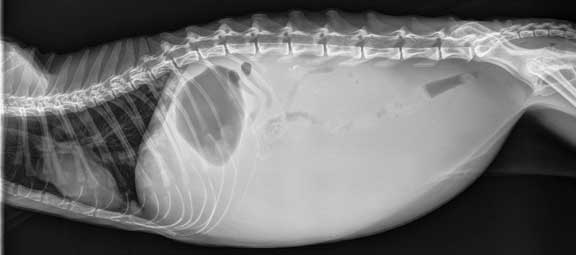

This picture is a good example. It is of a young cat with a distended abdomen. These are classic signs of FIP, and anyone online, as well-intentioned as they are, can easily jump to the conclusion that this is a case FIP in their zeal to sell you a treatment for FIP due to the tremendous financial incentive involved.

A pot-bellied abdomen can be perfectly normal in a kitten due to their musculature, so this might be normal. As it turns out, this cat has an internal parasite called Coccidia, and not FIP.

The following x-rays are of a normal cat first, and then one with the wet form of FIP. Approximately 100 ml (3 ounces) of fluid was removed from the chest of the cat with the fluid. After the fluid was removed it was analyzed because other diseases can cause fluid in the thorax (pleural effusion) also.

This is an x-ray of a normal cats thorax. This cat is laying on its right side, the head is towards the left. You can see the heart and the black lung tissue in the shape of a triangle. The diaphragm (arrows) is the vertical line that separates the thorax on the left from from the abdomen on the right. The liver resides in the abdomen.

This cat has a significant amount of fluid in the thorax (pleural effusion), making it difficult to identify normal organs. You cannot see the heart or diaphragm, and the lung tissue is greatly reduced because of all the fluid. The lungs are unable to expand fully causing significant difficulty in breathing. This pet is very ill and has minimal breathing reserve. It needs immediate removal of the fluid.

After some of the fluid was removed it is possible to visualize more of the organs. There is more lung tissue present and the top of the diaphragm is now visible.

The fluid found in the wet form of FIP can also occur in the abdomen (ascites). In this radiograph, the evidence of fluid accumulation is subtle, but present.

The fluid build up in this cat’s abdomen is obvious. You cannot see any individual internal organs due to the fluid.